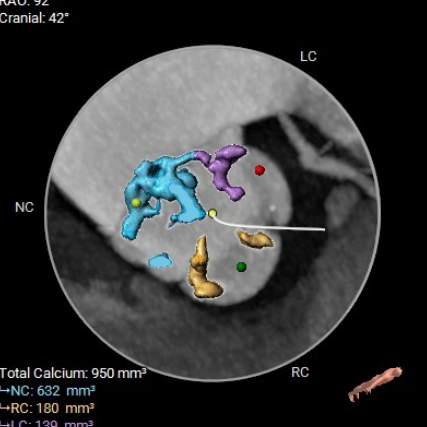

主动脉瓣钙化分布(钙化积分:950mm3)

左冠开口高度:

11mm

右冠开口高度:

16.2mm

● 主动脉根部:患者主动脉瓣为三叶瓣,左右冠窦可见部分粘连,重度钙化,瓣环到LVOT层面可见钙化,法式窦结构较大,左冠开口高度约11.0mm,右冠开口高度约16.2mm,STJ高度约19.5mm,直径约28.1mm,升主动脉未见明显扩张,心脏角度约49°,左室形态稍小,心肌增厚。

● 冠脉开口:左冠开口高度低,瓣叶长度可,窦宽相对瓣膜可;右冠开口高度可,瓣叶长度可,窦宽相对瓣膜可。冠脉风险低,建议球扩以进一步评估。

● 术后并发症风险:瓣叶钙化较重,瓣周漏风险高。